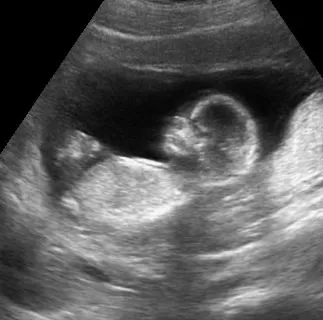

Die Sonographie ist eine beliebte Methode für werdende Eltern, sich vom Wohlbefinden und dem Wachstum des Kindes zu überzeugen und schon vor der Geburt eine intensive Bindung zum Kind aufzubauen.

Diese zusätzlichen Ultraschalluntersuchungen sind sicher medizinisch sinnvoll, aber nicht zwingend notwendig.

Wir sind gerne bereit – außerhalb der regulären Schwangerschaftsvorsorge – auf Ihren ausdrücklichen Wunsch hin, diese zusätzlichen sonograhischen Untersuchungen durchzuführen.